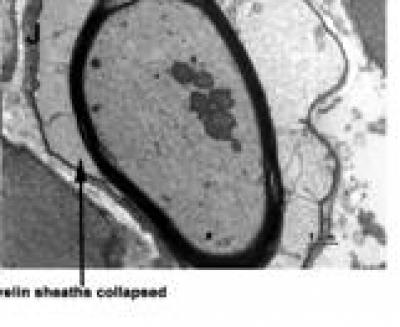

The use of iodine-125 (125I) in cancer treatment has been shown to relieve patients' pain. Considering dorsal root ganglia are critical for neural transmission between the peripheral and central nervous systems, Dr. Tengda Zhang and colleagues from Institute of Radiation Medicine, Chinese Academy of Medical Sciences, China assumed that 125I could be implanted into rat dorsal root ganglia (DRG) to provide relief for neuropathic pain. 125I seeds with different radioactivity (0, 14.8, 29.6 MBq) were implanted separately into the vicinity of the L5 DRG. Experimental results showed that the mechanical pain threshold was elevated after implanting 125I seeds without influencing motor functions of the hind limb, although cell injury was present. This article is released in the Neural Regeneration Research (Vol. 9, No. 12, 2014).

Article: " Implanting iodine-125 seeds into rat dorsal root ganglion for neuropathic pain: neuronal microdamage without impacting hind limb motion," by Ling Jiao1, Tengda Zhang1, Wenting Ma2, Huixing Wang2, Wenyi Zhang1, Saijun Fan1, Xiaodong Huo2, Baosen Zheng2 (1 Institute of Radiation Medicine, Chinese Academy of Medical Sciences, Tianjin, China; 2 Second Affiliated Hospital of Tianjin Medical University, Tianjin, China)